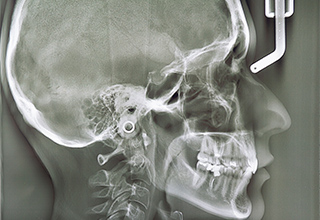

セファログラム

(頸部x線規格写真)

頭蓋骨のレントゲン写真を撮影することで、歯列弓や上下顎の位置•骨格の成長の変化や歯の移動などを分析することができます。そのため、より正確な矯正治療をすることができます。